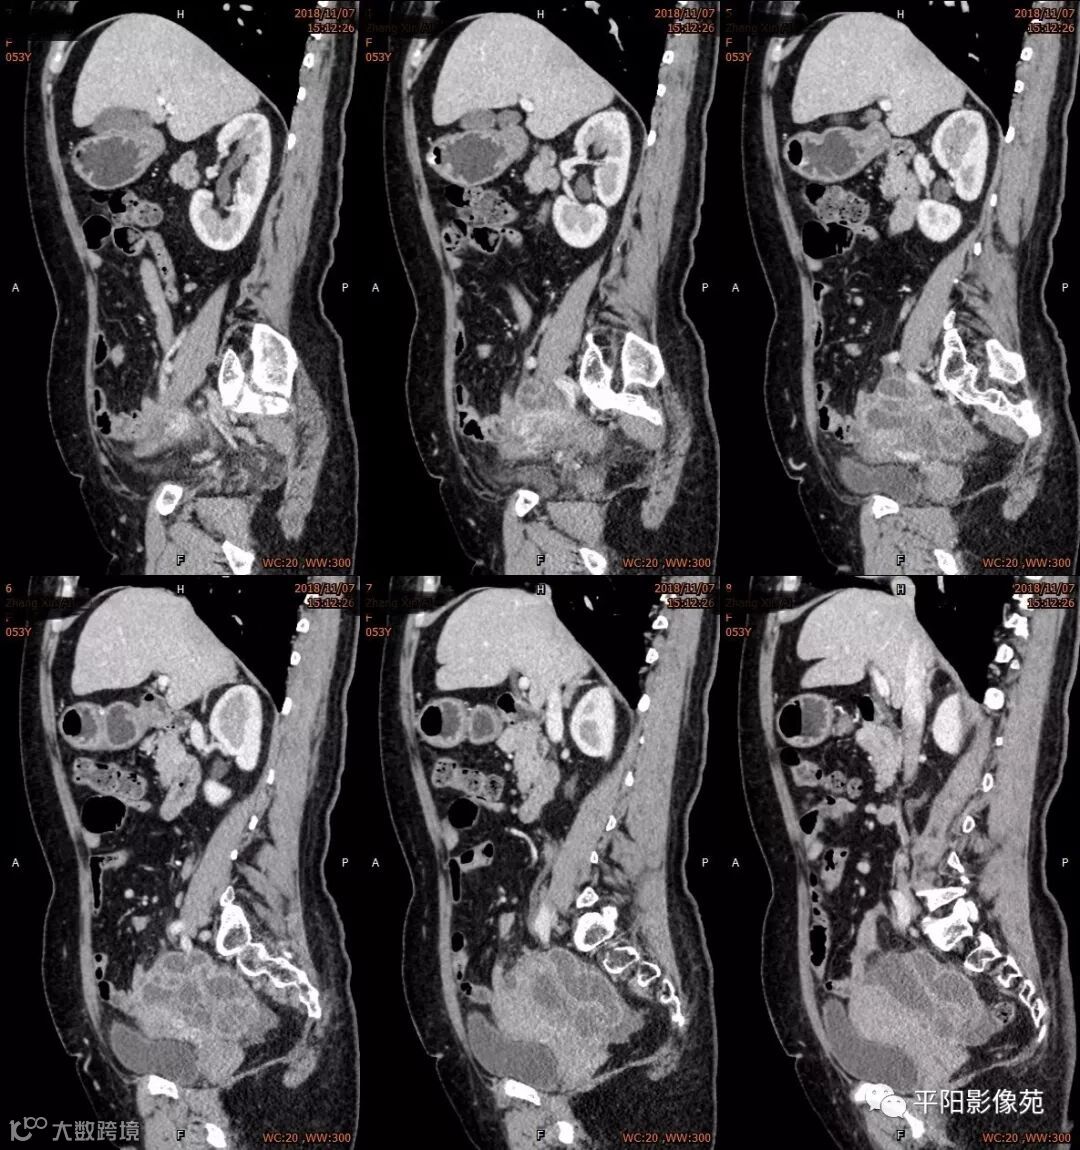

影像特点

右附件区薄壁囊性病变,壁明显强化,边界不清,供血动脉源自子宫动脉,且局部动脉血管增多;其内侧可见卵圆形无强化囊性病灶。

附件区病变多见于卵巢,以囊性为主的病灶多为卵巢囊肿、粘液/浆液性囊腺瘤、皮样囊肿等,这些病灶都具有鲜明瘤体结构,且壁强化多为轻-中度,供血动脉多源自卵巢动脉;而本例患者右附件区薄壁囊性病灶,多位置观察形态为迂曲管状,且壁有明显延迟强化,供血动脉源自子宫动脉,较对侧血管丰富,故而考虑源自输卵管或子宫病变,但子宫发生的薄壁囊性病变较少,多见于子宫肌瘤囊变,完全囊变者少见,且形态轮廓与肌瘤相同为球形故而排除,结合患者腹痛前有感冒病史,且有压痛,因此考虑输卵管积脓可能。其内侧无强化囊性肿块,考虑卵巢囊肿可能。

主要与卵巢囊肿伴感染、皮样囊肿、卵巢囊腺瘤等鉴别,当病变表现相似时,可根据供血动脉以兹鉴别,卵巢病灶为卵巢动脉供血,其自腹主动脉,输卵管病变多由输卵管动脉供血,源自髂内动脉→子宫动脉→输卵管动脉。